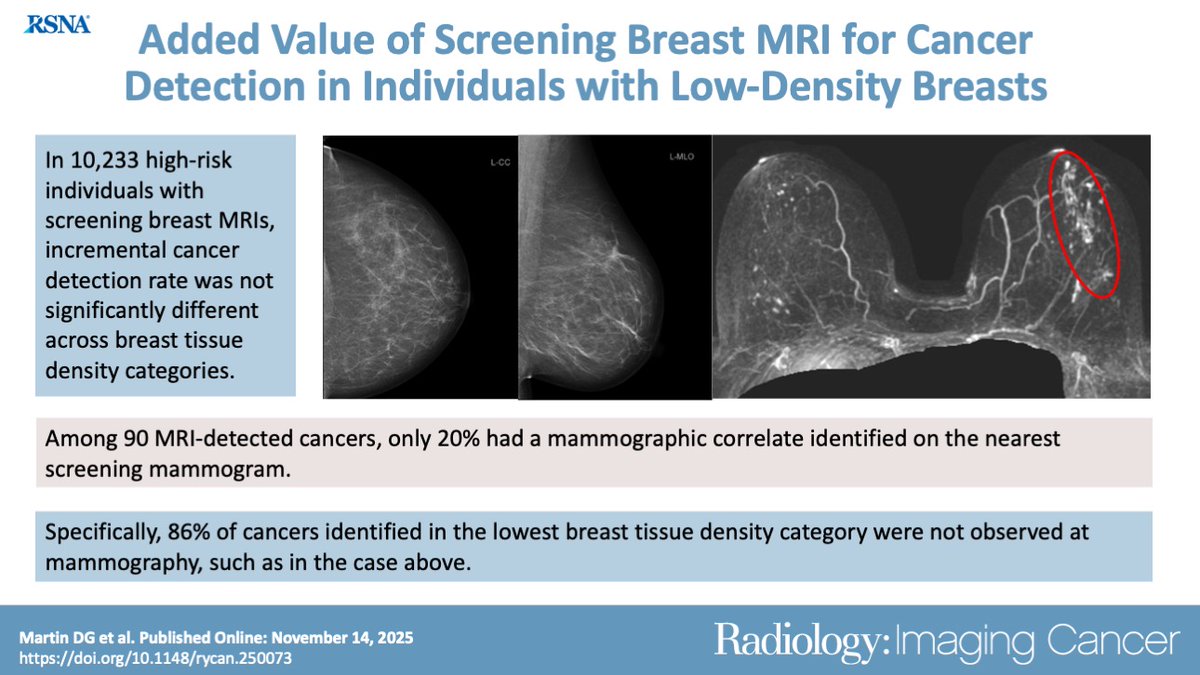

Study underscores need for #BreastDensity Notification HIQA Marie Keating Foundation Irish Cancer Society National Cancer Registry Ireland "Women with extremely dense breasts or heterogeneously dense breasts had significantly higher false-negative rates" diagnosticimaging.com/view/mammograp…